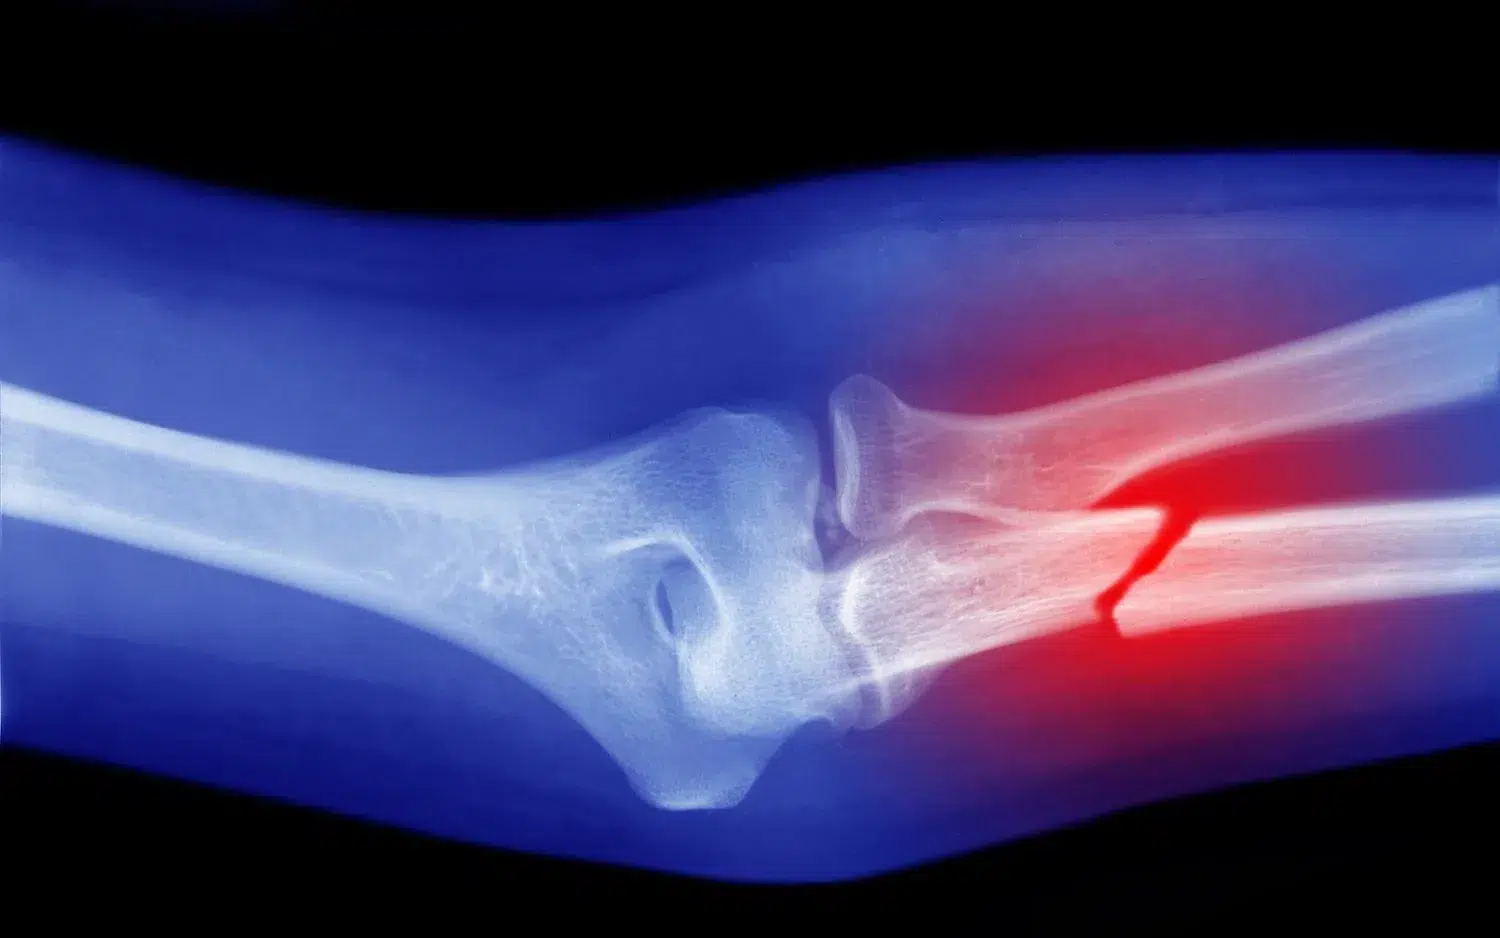

Broken bones, also known as fractures, can occur in various ways. Car accidents, slip and falls, workplace incidents, and sports injuries are just a few examples. These accidents can lead to fractures in different parts of the body, such as the arms, legs, wrists, and ankles.

When you break a bone, the pain can be excruciating. It can interfere with your daily activities, work, and overall quality of life. In some cases, fractures require extensive medical treatment, including surgeries, rehabilitation, and long periods of rest.

Broken bones can vary in severity, from hairline fractures to compound fractures that require immediate medical attention. Some common types of broken bone injuries include:

3. Leg Fractures: These can range from simple fractures to more complex injuries, such as femur fractures, which may require surgery.

4. Arm Fractures: Falls, car accidents, and workplace incidents can cause arm fractures, affecting the humerus, ulna, and radius bones.